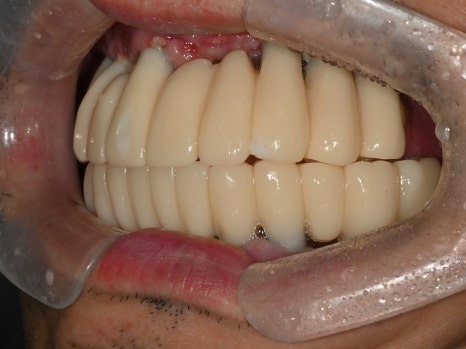

수술 후

디지털 방식으로 제작된 임시치아

8개의 전체임플란트를

하루에 바로 수술할 수 있었고,

병원 내의 디지털기공소에서

바로 임시치아를 제작하였습니다.

수술 전

수술 1일 후

하루만에 위턱 전체 치아가 생겨서

식사가 바로 가능하시게 되자

환자분은 너무 놀라워하시고 좋아하셨습니다.